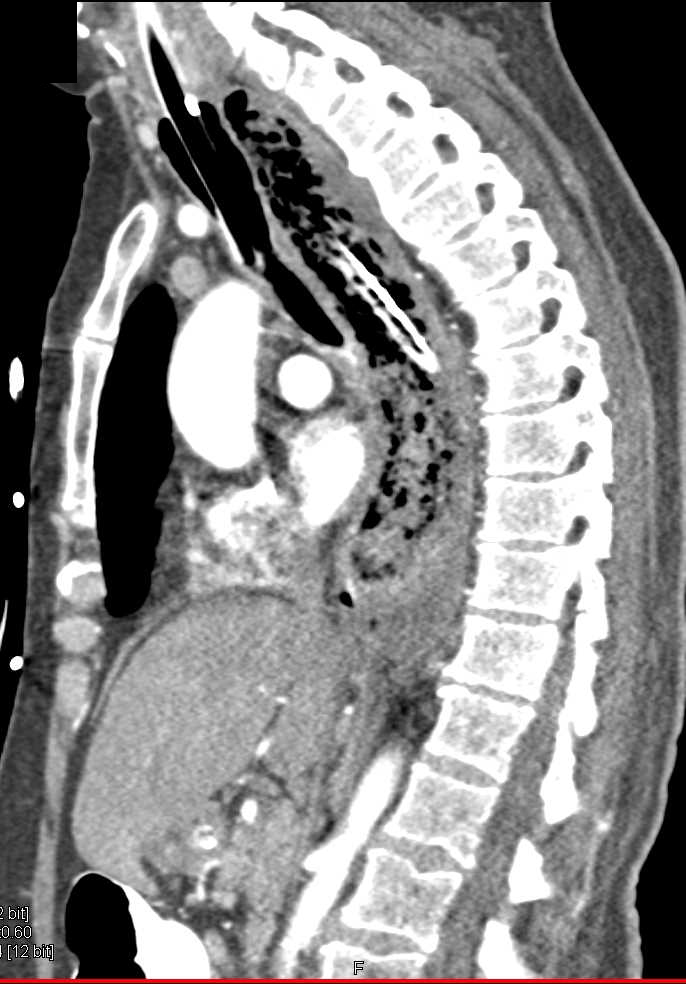

Esophageal Perforation